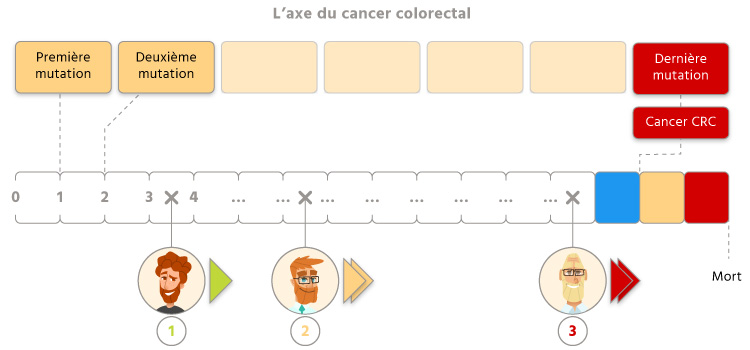

Le cancer du côlon, ça n’est pas quelque chose qui surgit de nulle part, un beau matin. Au départ, c’est une simple cellule du côlon qui est endommagée et qui transmet son « défaut » à certaines de ses semblables. Mais jour après jour, année après année, cette cellule hérite de nouveaux défauts qui s’accumulent et qui provoque des dysfonctionnements de plus en plus importants, jusqu’à ce que l’ultime mutation provoque l’irréparable : l’apparition d’une incontrôlable cellule cancéreuse. Pour mieux comprendre ce phénomène, on peut le représenter par une flèche chronologique, avec tout à gauche la première mutation qui va initier le processus, et tout à droite la dernière qui va faire apparaître la tumeur. Entre ces deux événements, il peut se passer 10, 20 ou même 50 ans, mais quoiqu’il arrive, nous avons tendance à accumuler les mutations avec le temps et dériver lentement vers la droite de cet axe.

Que se passe-t-il ensuite pour eux ? Tout va dépendre de leur réactivité. Si ces personnes mettent trop de temps à déceler les cellules cancéreuses qui se multiplient à leur insu dans le côlon, elles continuent de dériver vers la droite de la flèche, se rapprochant cette fois d’un point de non-retour : la mort. Chaque année, 18 000 personnes empruntent cette voie funeste à sens unique.

En revanche, si la tumeur est détectée alors qu’elles se trouvent encore suffisamment proche du point d’apparition (dans la « zone d’urgence »), elles peuvent encore espérer échapper au pire. La prise en charge médicale permet en quelque sorte d’arrêter la progression, et en cas de guérison, elles retournent vers l’arrière, à une certaine distance du cancer colorectal.

C’est la première bonne nouvelle : la rapidité avec laquelle nous dérivons vers le cancer du côlon est différente pour chacun de nous. Les plus rapides peuvent atteindre l’autre extrémité en moins de 40 ans, tandis que certains ne parviennent jamais jusque-là au cours de leur vie.